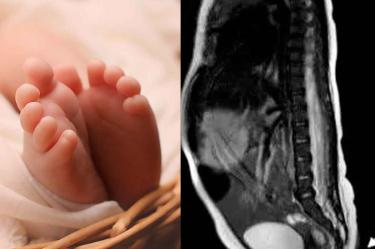

El nacimiento de una bebé en un hospital de Nuevo León dejo boquiabiertos a los médicos cuando advirtieron que la recién nacida vino al mundo con una colita.

De acuerdo con el informe del nacimiento la pequeña poseía una cola "extremadamente rara" cuya longitud era de 5.7 cm y su diámetro era de entre 3 mm y 5 mm en su longitud, cilíndrica y puntiaguda hasta el final.

A la mamá se le practicó cesárea mientras que los doctores encargados del parto no ocultaron su sorpresa cuando se percataron de que tenía una colita “suave, cubierta de piel, pelo fino y forma puntiaguda”.

Luego de una radiografía, no se evidenció alguna anomalía o estructura ósea dentro de la extremidad, lo que sugiera que no es vestigial.

Los especialistas explicaron además que la cola no fue resultado de un problema en la columna, como sucede en el disrafismo espinal que evita que el giro se forme correctamente y aparezca un crecimiento similar a una cola en la parte inferior de la columna.